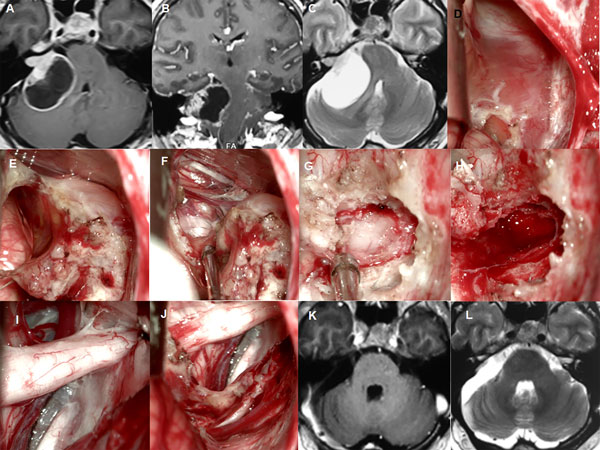

Figura 3: Paciente femenino de 40 años, operada de SV T3b izquierdo. A-B: RM preoperatoria. C-F: hallazgos intraoperatorios. G: RM postoperatoria, H: imagen intraoperatoria del lecho tumoral y descompresión del complejo VII-VIII

Figura 4: Paciente femenino 20 años, operado de SV T4b derecho. A-C: RM cerebral preoperatoria, D-I: imágenes intraoperatorias, D-F descompresión intratumoral con aspirador ultrasónico, G-H descompresión del complejo VII-VIII, I: oclusión del CAI con cola de fibrina. J-L: RM cerebral postoperatoria

Figura 5: Paciente masculino de 18 años, operado de SV T4b bilateral. A-C: RM cerebral preoperatoria. D-I: imágenes intraoperatorias (lado derecho), D-F descompresión intratumoral con aspirador ultrasónico, G-H descompresión del complejo VII-VIII, I: oclusión del CAI con cola de fibrina., J-L: RM cerebral postoperatoria

Figura 6: Paciente femenino de 72 años, operado de SV T3b con quiste externo. A-C RM preoperatoria, D-I: imágenes intraoperatorias, D-F descompresión intratumoral con aspirador ultrasónico, G-H descompresión del complejo VII-VIII, J-L: RM cerebral postoperatoria.

Figura 7: Paciente masculino de 37 años, operado de SV T4b derecho con quiste externo. A-C: RM cerebral preoperatoria. D-J: imágenes intraoperatorias, K-L: RM cerebral postoperatoria